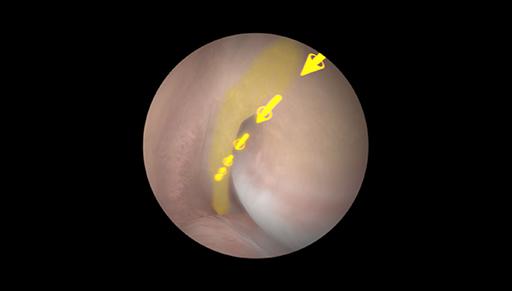

Learn instrument handling and triangulation skills while avoiding cartilage damage. Learn to visualize relevant structures with an arthroscope, palpate them with a probe, and resect them with a punch and shaver. Helping elements such as colors and arrows guide you through the case. Treat simple meniscus lesions, combined arthrosis and tears, synovitis, loose bodies. Objective feedback reports provide learners with essential information on how well they performed the procedure and which aspects to focus on next time.